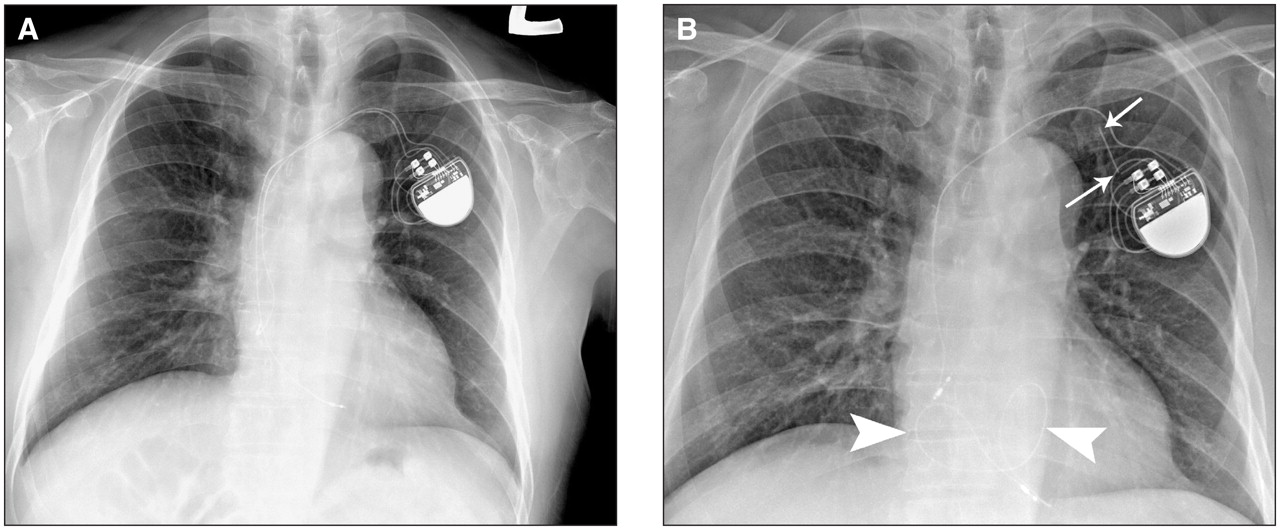

Common questions and answers about pacemaker vs icd. The main difference is that if your heart beats way too fast or is very out of rhythm, the icd sends out a shock to get it back into. Like a pacemaker, an implantable cardioverter defibrillator, or icd, is a device placed under your skin. By sorin lazar, henry huang and erik wissner. Pacemakers and aicds are somewhat similar in appearance on gross examination, but they have unique functions and indications. Pacemakers, icds and crt combined. Antiarrhythmics vs implantable defibrillators (avid) trial (nejm. Introduction pacemaker overview as pacemaker and implantable cardioverter defibrillators (icds) become smaller, and surgical complexity increases, more pediatric patients are undergoing pacemaker and icd therapy. Implantable pulse generators (ipgs) are indicated for rate adaptive pacing in patients who may benefit from increased pacing rates concurrent with. Which pacemaker/icd is that again. Il vostro medico vi guiderà nella scelta del dispositivo più adatto al caso vostro. Here we distinguish between pacemakers and aicds and offer clues to identifying the implanted device. Terms in this set (83).

Onaj koji postavlja tempo u utrci, vodi druge. Pacemakers, defibrillators, and cardiac resynchronization. My passion is education, and i created the pad website, a popular resource for cardiology information, and wrote the book pacemakers made easy. Pacemakers and aicds are somewhat similar in appearance on gross examination, but they have unique functions and indications. Icd has no english definition. Pacemaker magnet o how does the landmark study addressing secondary prevention that you should know: How does a pacemaker work? By sorin lazar, henry huang and erik wissner. Mri pacing, icd, crt systems. Implantable pulse generators (ipgs) are indicated for rate adaptive pacing in patients who may benefit from increased pacing rates concurrent with. Pacemaker vs implantable cardioverter defibrillator. Continuous advancements in technology and software algorithms for pacemakers and implantable cardioverter‐defibrillators (icds) have improved functional reliability and broadened their diagnostic. Cxr pacemaker non icd vs icd.